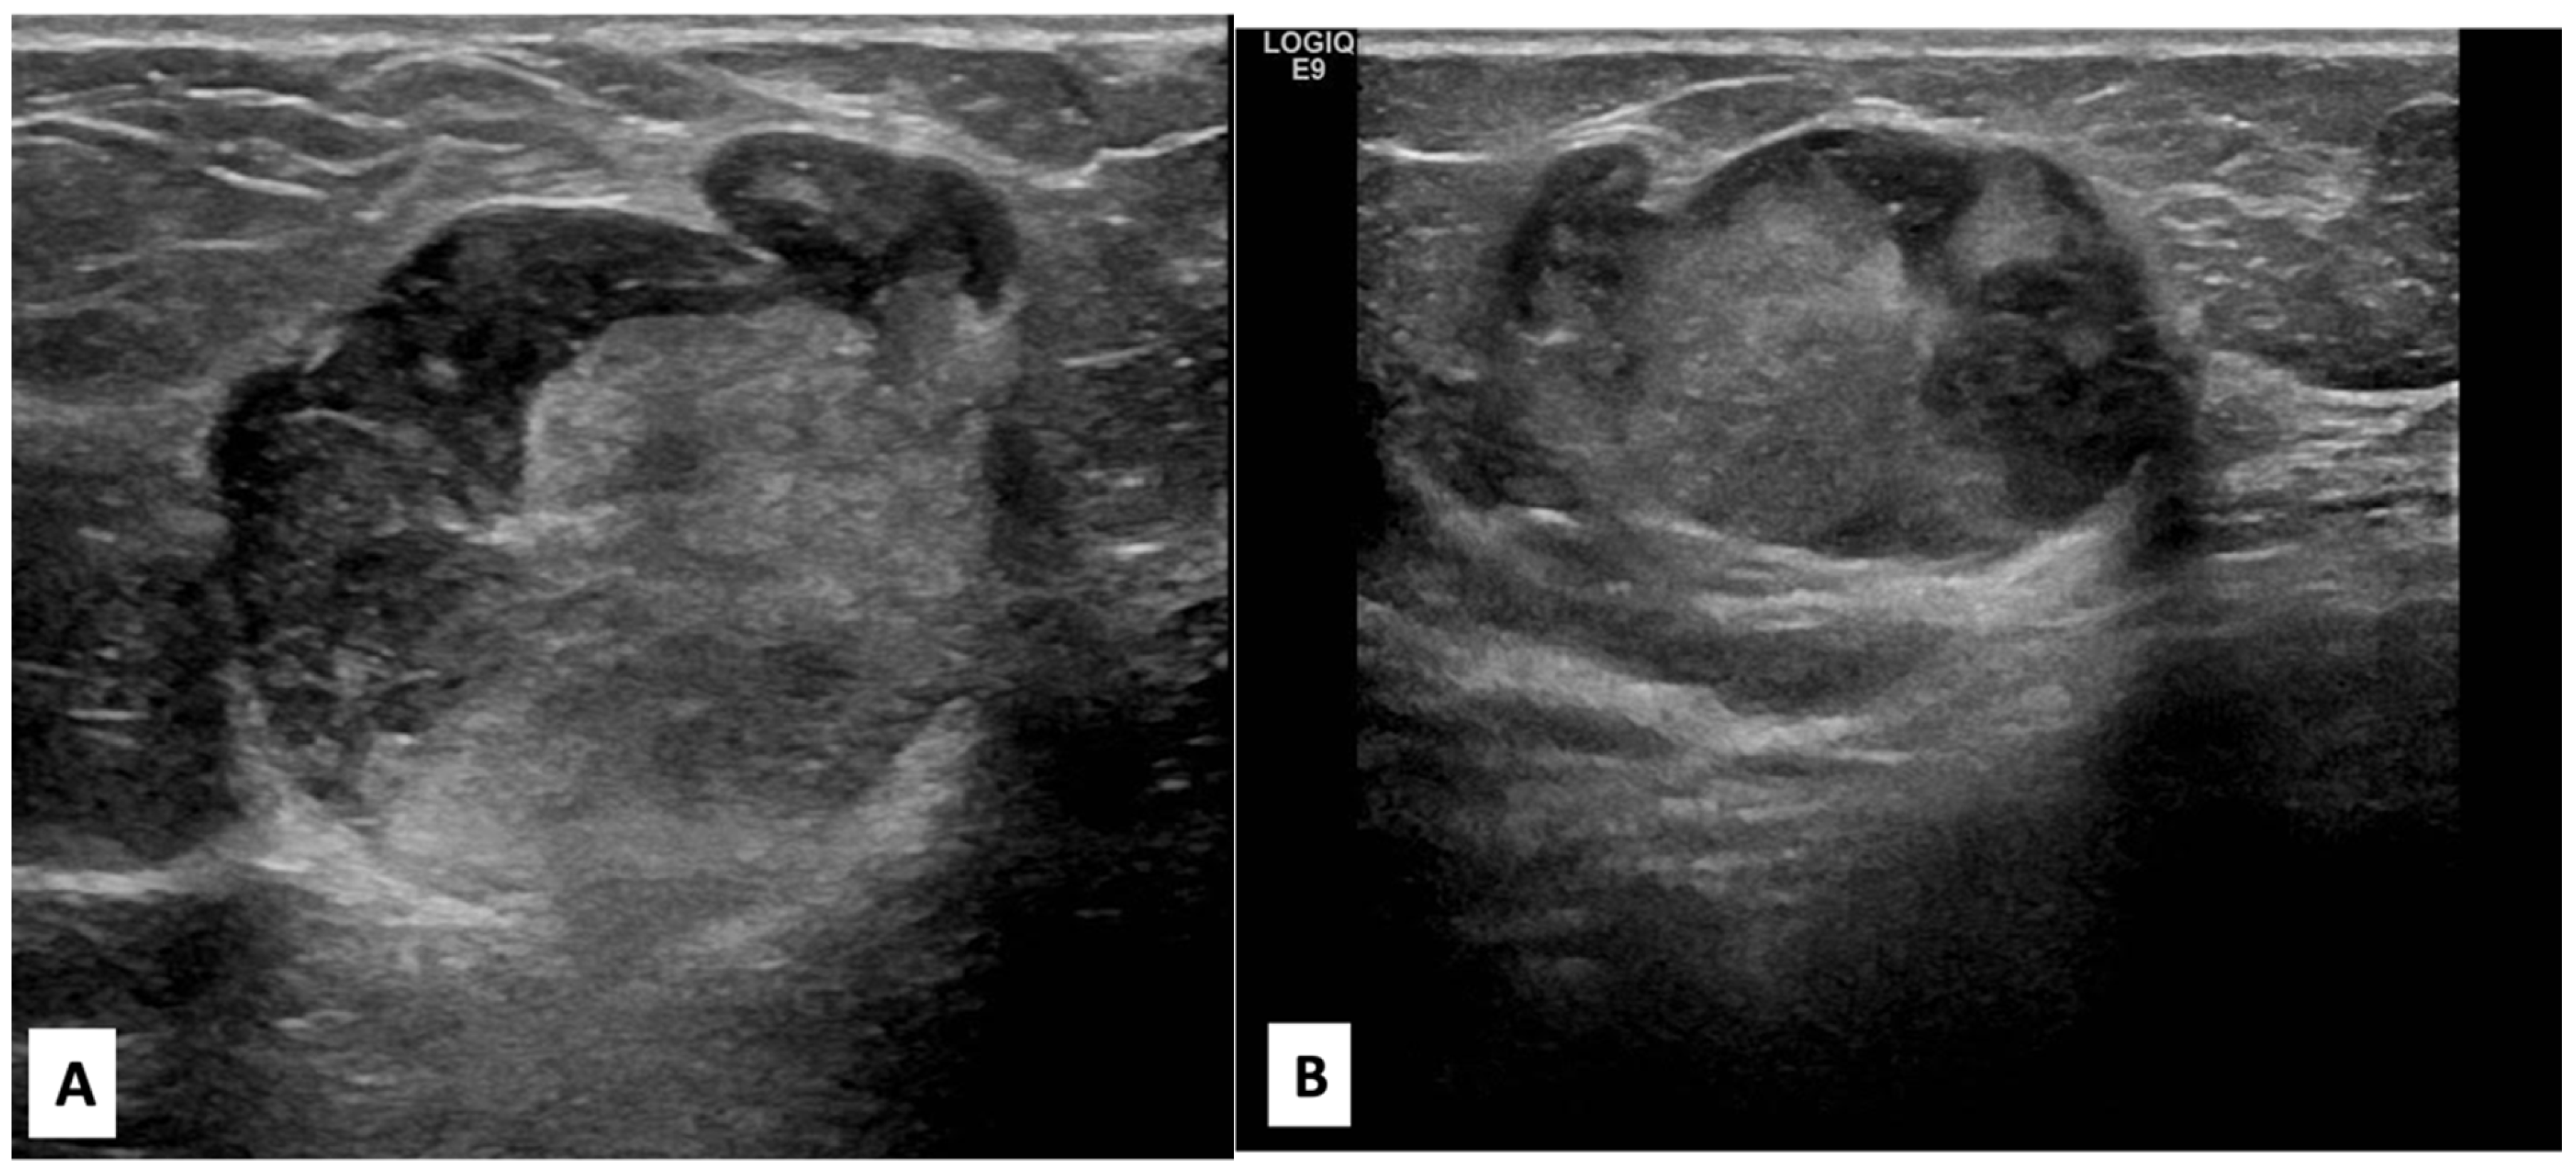

There was no indication of inflammation or swelling in either breast. A mammogram showed a large fat-containing oval-shaped lump with a circumscribed outline, and the mass in the upper outer quadrant of the right breast was approximately 9 cm from the nipple and measured 3 × 3.5 cm2 (Figure 2). However, mammography of the left breast showed nothing out of the ordinary. The subsequently targeted ultrasonography (US) revealed a heterogeneous isoechoic irregularly shaped solid mass that measured 3.3 × 3 cm2 and had eccentric cystic foci placed at the 9 o’clock position and approximately 8 cm away from the nipple (Figure 3). Differential diagnoses include phyllode tumor (PT) in addition to liposarcoma. The patient sought treatment at a tertiary hospital, where she underwent a right breast biopsy, and based on the findings of that procedure, a right lumpectomy without an axillary dissection was conducted. When seen under a microscope, the tumor was found to contain mature adipocytes, atypical spindle cells, and multivacuolated lipoblasts. All of these cell types were discovered to be embedded in a loose myxoid to fibrous stroma within the tumor itself. This information is provided by the pathology report. In addition, there were a significant number of regions that had pleomorphic cells, multinucleated, weird, enormous cells, and lipoblasts (Figure 4 and Figure 5).

Figure 2. Craniocaudal and mediolateral oblique nine-month follow-up mammography of the right breast. (A,B) A large, circumscribed fat-containing oval-shaped lump approximately 9 cm from the nipple measuring 3 × 3.5 cm2 (arrows) with no associated suspicious features (suspicious microcalcification or architectural distortion).